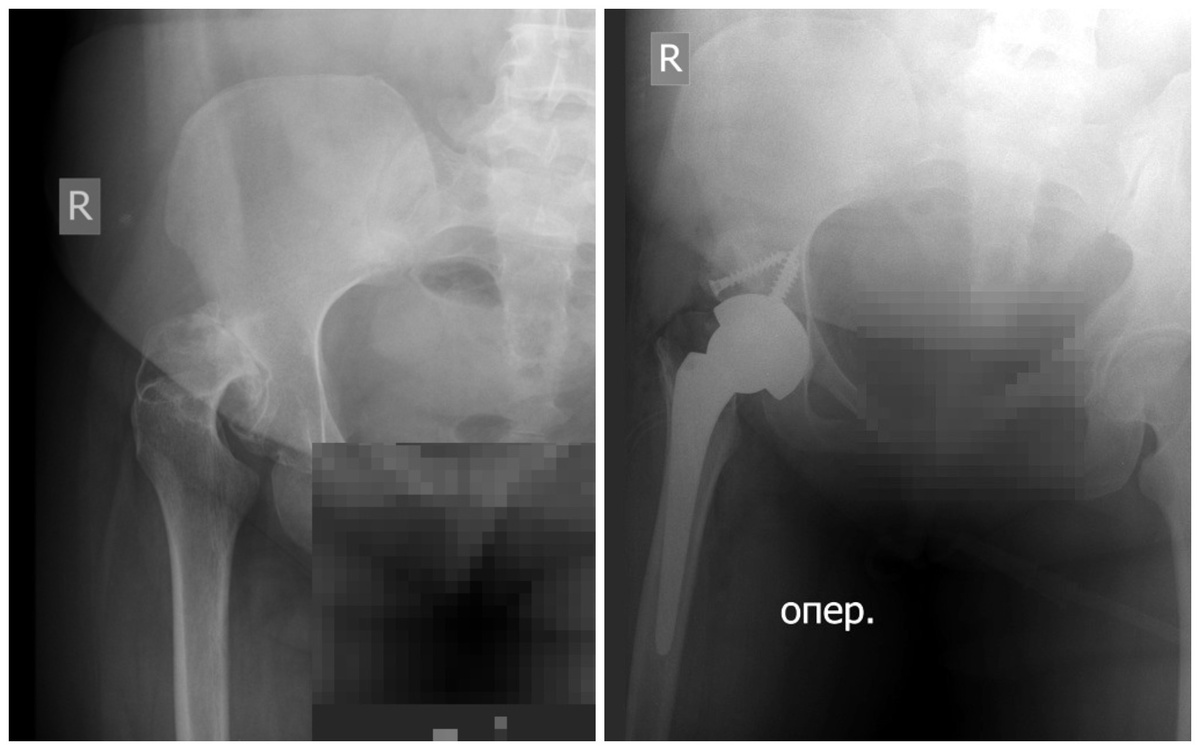

Само выполнение операции не представляет больших сложностей - это достаточно стандартное протезирование. Однако для проведения такой операции есть четкие критерии отбора пациентов:

• артроз суставов 3-4 стадии

• обязательно ходячий, интеллектуально сохранный пациент, со слабой спастичностью

• уровень 1-3 по шкале GMFCS*

Для данного оперативного вмешательства на тазобедренных суставах требуется специальный тип протезов с двойной мобильностью. Главное отличие от стандартных имплантатов — полиэтиленовый вкладыш, который создает дополнительный уровень подвижности. Он толще, чем у традиционных моделей, что снижает риск вывиха и увеличивает срок службы эндопротеза. Благодаря этому механизму нагрузка на сустав распределяется равномернее, а риск вывиха.

Еще одной специфической для нейроортопедической патологии проблемой является отсутствие должного моторного контроля над мышцами и двигательной активностью у пациентов с церебральным параличом. Особенно это выражено при 4 и 5 уровне GMFCS*, что делает практически невозможным эффективное эндопротезирование с долгим сроком службы имплантата. Поэтому в современных реалиях эффективное эндопротезирование у людей с ДЦП доступно лишь пациентам 2-3 уровня GMFCS*. Эта когорта молодых людей с достаточным моторным контролем двигательной активности, возможностью вертикализации и ходьбы, отсутствием тяжелого остеопороза.

При наличии всех перечисленных показаний к операции врачи рекомендуют выполнять эндопротезирование в более позднем возрасте, чтобы отсрочить время ревизионной операции.